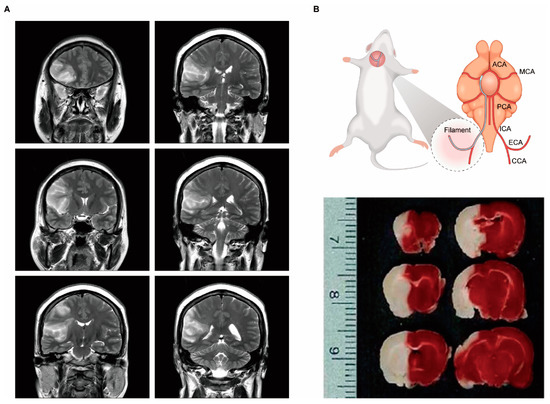

- Sommer, C.J. Ischemic stroke: Experimental models and reality. Acta Neuropathol. 2017, 133, 245–261. [Google Scholar] [CrossRef] [PubMed]

- Fluri, F.; Schuhmann, M.K.; Kleinschnitz, C. Animal models of ischemic stroke and their application in clinical research. Drug Des. Devel. 2015, 9, 3445–3454. [Google Scholar] [CrossRef]

- Rupadevi, M.; Parasuraman, S.; Raveendran, R. Protocol for middle cerebral artery occlusion by an intraluminal suture method. J. Pharm. Pharm. 2011, 2, 36–39. [Google Scholar] [CrossRef]

- Liu, F.; McCullough, L.D. Middle cerebral artery occlusion model in rodents: Methods and potential pitfalls. J. Biomed. Biotechnol. 2011, 2011, 464701. [Google Scholar] [CrossRef]